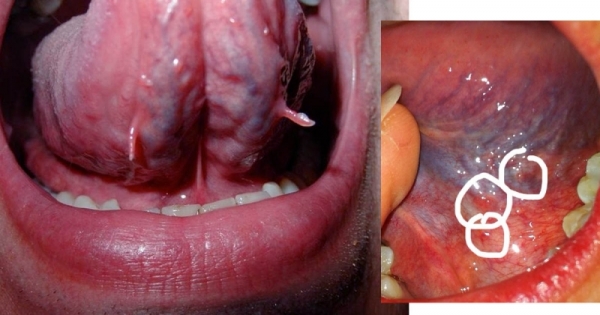

先來看看舌頭的結構。

一看就明白:原來我們每個人舌下都有很多淺表的舌下靜脈叢!

再來分析一下舌下的「青筋」。

1,如果舌下的「青筋」每天幾乎一樣,不是突然增加,沒有出血,沒有異常的突起,也沒有任何不適的癥狀,這就是正常的,不需要治療;

2,如果的確是最近一段時間突然增加的,要考慮飲食和睡眠是否沒有規律,生活工作壓力太大。

3,如果是近期出現的舌下靜脈曲張,比過去更加凸起,有可能是本身的血管功能不太好,一般來說這個提示可能有血管方面的問題,比如冠狀動脈阻塞,心機功能不夠強大。

4,如果是深青、紫暗或紫黑色,提示可能有淤血,即使是無結節、無明顯扭曲,也可能是血液毒素積累的原因導致的;中醫稱之為血瘀證,與中醫的肝病有關;